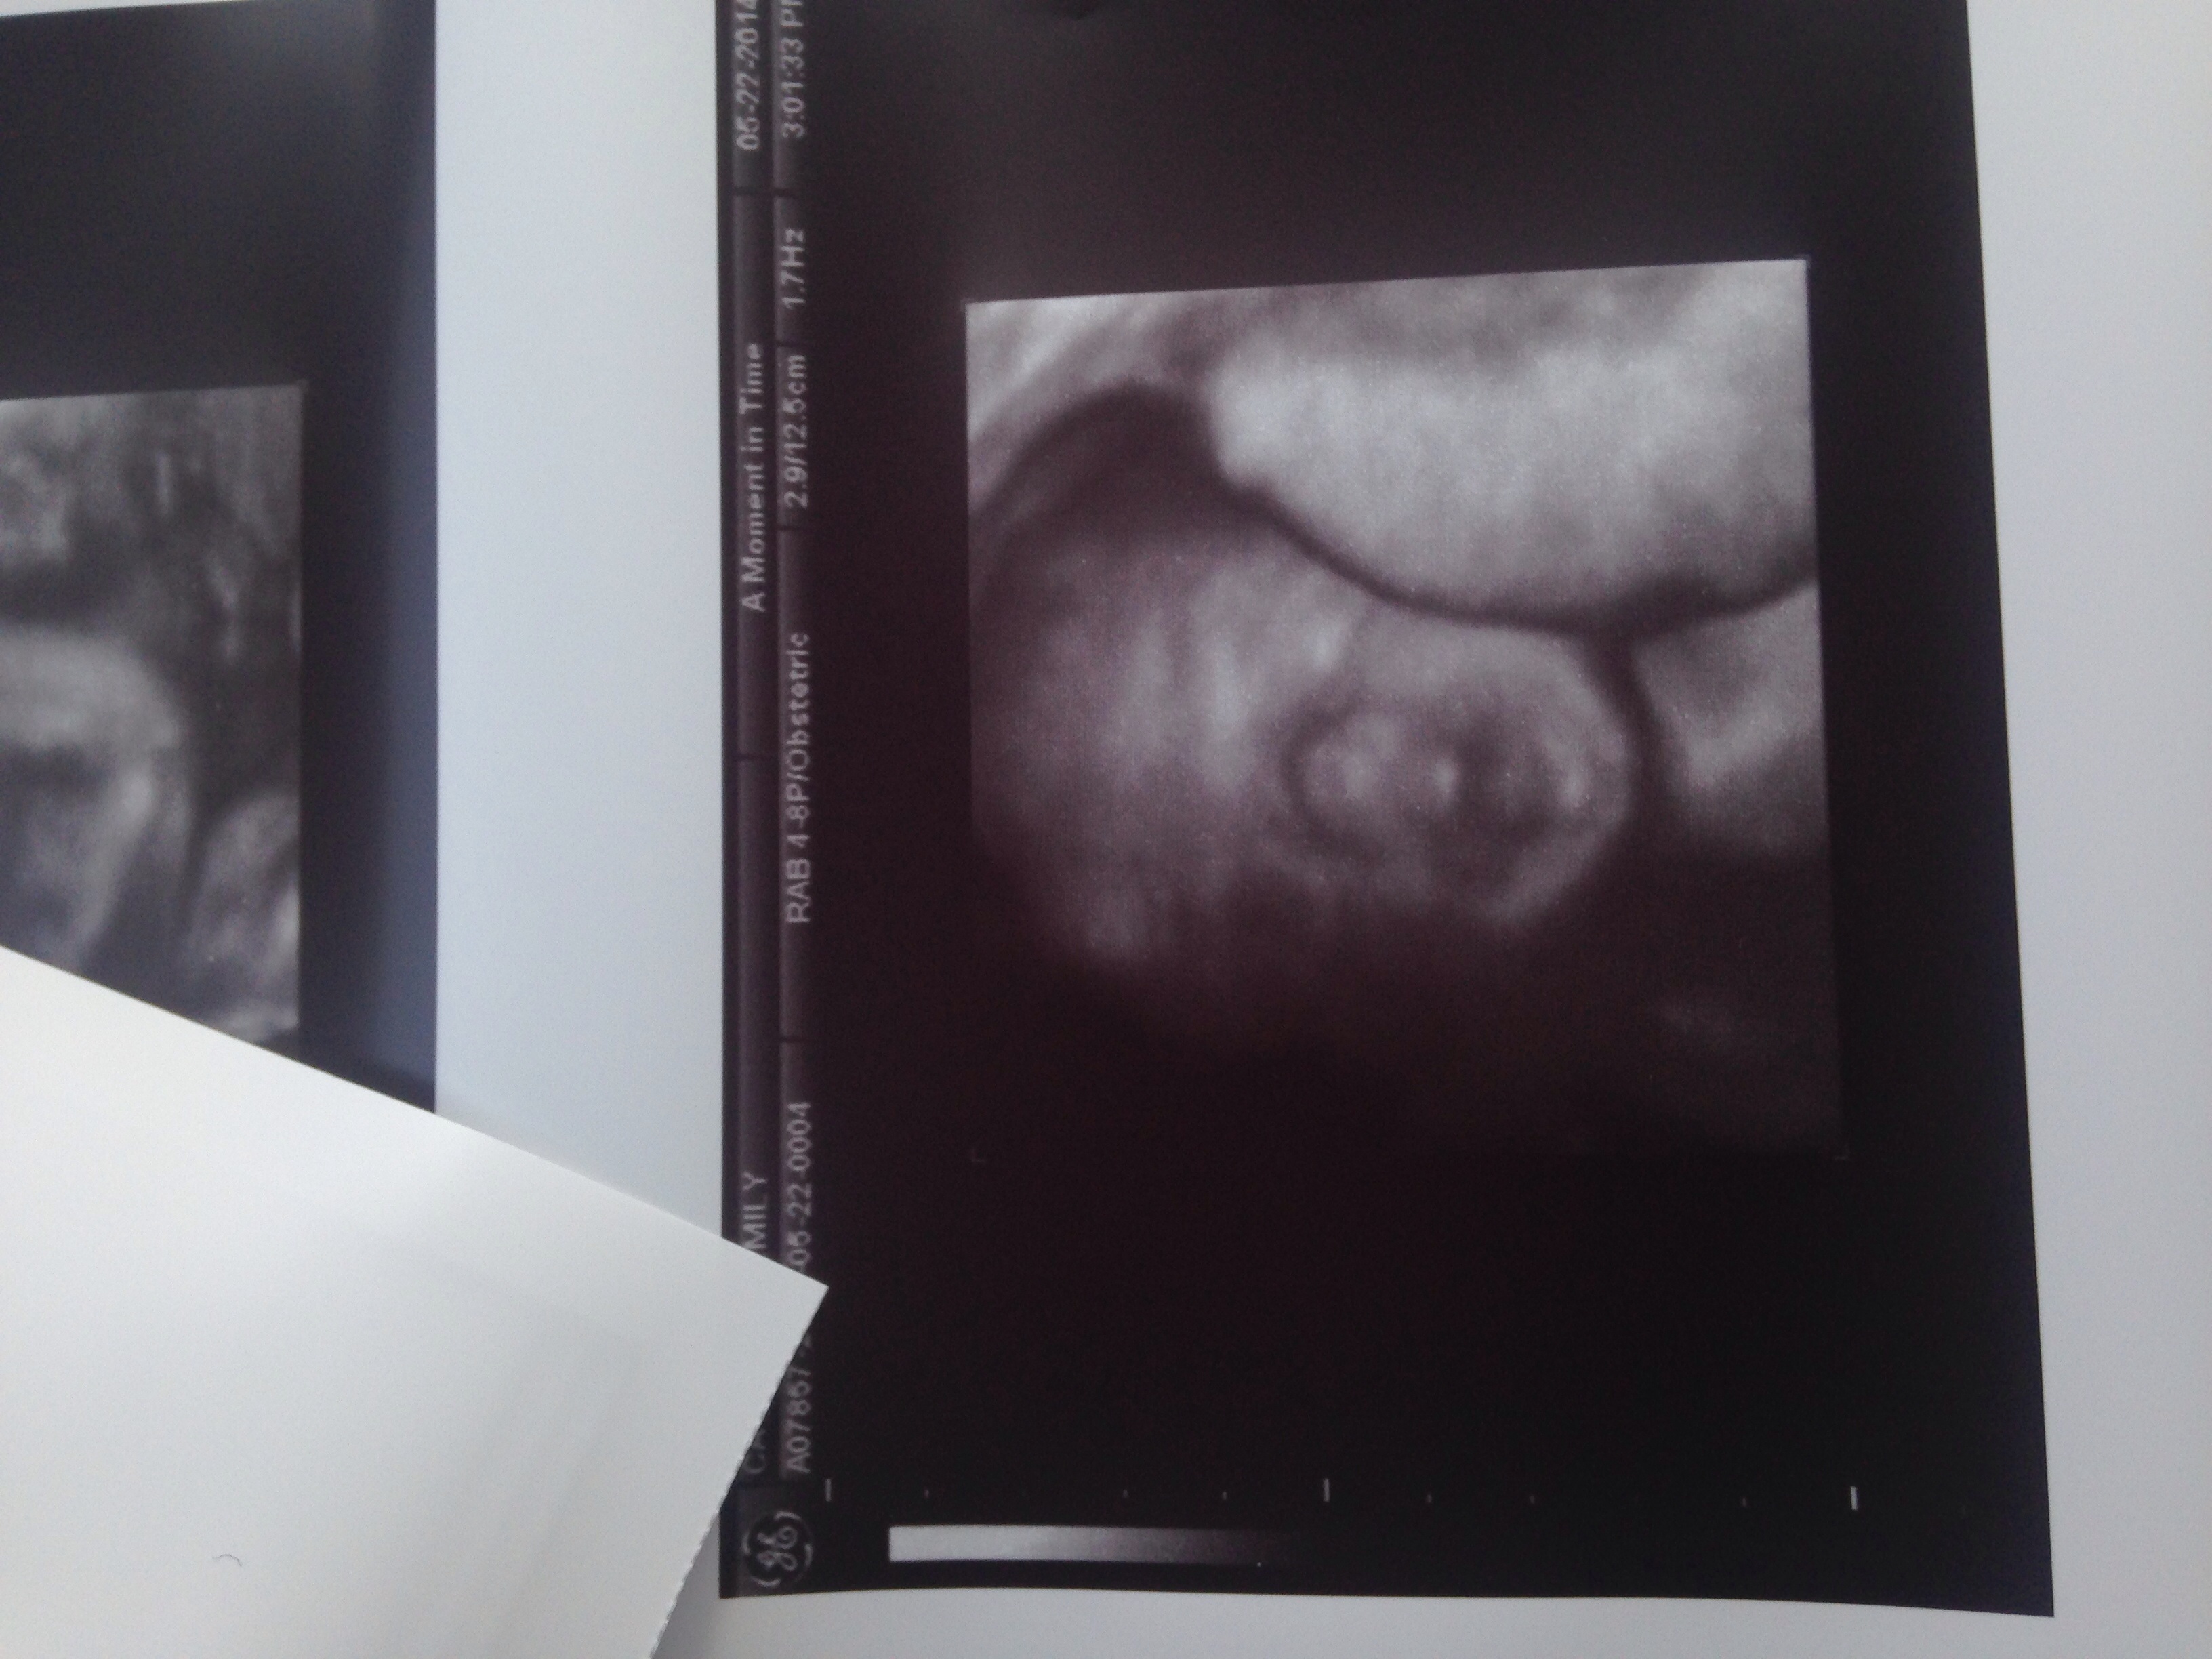

AW: 3D ultrasound picture

So she looks like her sperm donor 100% but hey she's frackinnnnn CUTE!

image.jpg